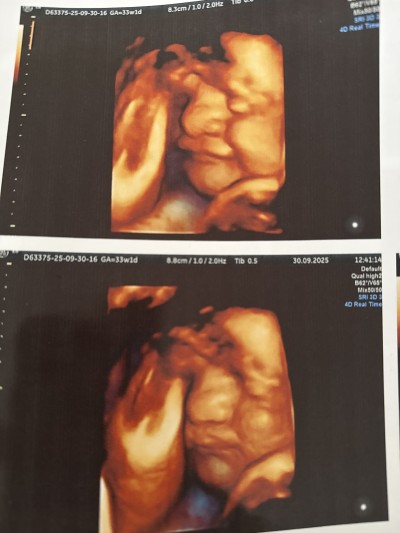

Burnu çok büyük doğunca böylemi oluyor?

Gebelik haftası 33